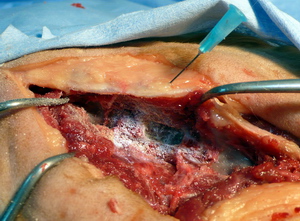

Fresado inicio

Fresado ventana

Cortical profunda